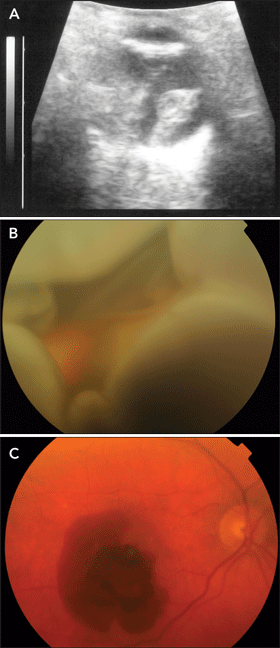

Age-related macular degeneration affects about one-third of people aged over 75 years.1 Of those with AMD, 10%–15% develop the neovascular (“wet”) form,2 characterised by abnormal new blood vessel formation in the choroid, under the retina. These abnormal vascular membranes are prone to rupture, leading to subretinal bleeding, fibrous scar formation and severe visual loss.

Many older patients who have AMD also take medications that can exacerbate or promote bleeding, such as anticoagulants or antiplatelet agents. In rare cases, intraocular bleeding — in the form of subretinal, suprachoroidal, or vitreous haemorrhage — can be catastrophic and blinding. Previous reports link systemic anticoagulation therapy to intraocular haemorrhage and blindness in AMD patients,3-7 including a recent report in this Journal.8 In two of these reports, patients taking warfarin had very high INRs (4.1 in one case;3 6.3 in the other4).

Other reports link systemic anticoagulation therapy to spontaneous suprachoroidal haemorrhage, even in the absence of neovascular AMD.9-11 Additionally, patients with neovascular AMD can develop massive submacular haemorrhage, even if they are not taking antiplatelet or anticoagulant agents. Unfortunately, as many patients with AMD have one eye with poor visual acuity due to macular scarring, it is all the more catastrophic when a massive haemorrhage leads to blindness in their “good” eye.